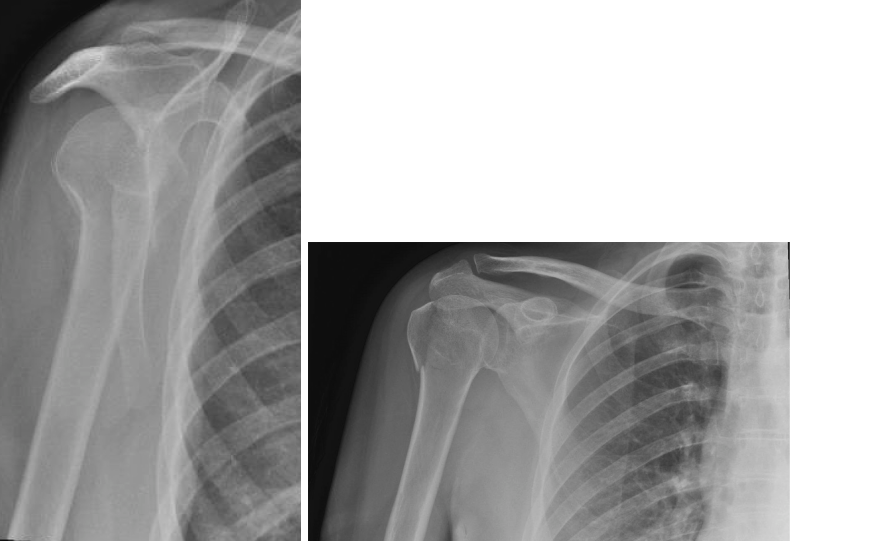

A 32-year-old woman is admitted after a fall from her bicycle. She has an isolated injury to her left upper l…

Quiz on Monteggia Fracture Dislocation 1. Describe the appearances shown in these radiographs. Show Answer Th…

A 35-year-old woman fell from a ladder, injuring her right shoulder. These are her radiographs. 1. What do th…